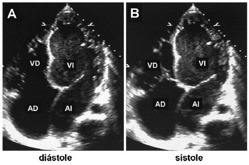

Ecocardiografía 2D. Marcada dilatación de las cavidades cardíacas.

Ecocardiografía modo M. Severa dilatación de los diámetros diastólicos (dd) y sistólicos (ds) del ventrículo izquierdo (VI) con pobre contractilidad.